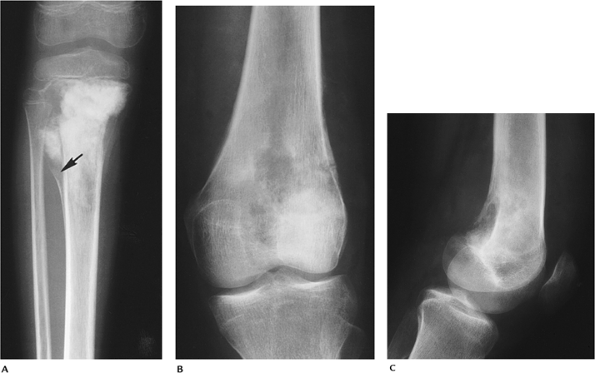

FIGURE 10-28

Telangiectatic osteosarcoma. AP radiograph demonstrating a permeative lytic lesion in the proximal tibia with pathologic fracture medially (arrow). |

P.685

![]() |

|

FIGURE 10-29 Telangiectatic osteosarcoma. AP (A) and lateral (B) radiographs showing a permeative lesion with aggressive periosteal reaction. Coronal T2-weighted (C) and axial T1-weighted (D) MR images showing a large soft tissue mass with multiple fluid intensity collections on T2-weighted image (C).